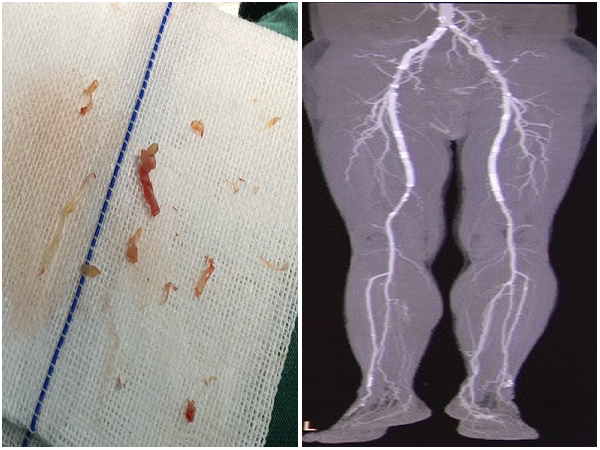

患者张先生,68岁,10余前无明显诱因出现双下肢行走后疼痛、发凉。7年前至北京某三甲医院诊治,并给双下肢共植入7枚支架,术后效果好。但半年前再次出现行走后双下肢疼痛,休息后缓解不明显,伴发凉、麻木症状,左下肢行走距离约200米,右下肢约100米。张先生及家人辗转多家医院无果,后经大夫推荐急来郑州大学五附院诊治。患者治疗难点是支架内及近远端广泛内膜增生,普通外科手术及介入治疗束手无策。经积极术前准备后王兵教授带领血管外科崔文军副主任、吴斐、王颖等医师给患者实施了双下肢动脉Turbo Hawk斑块旋切术。术中克服重重困难,反复切除内膜及斑块,杀出一条血路,打通了双下肢狭窄闭塞段,取得了满意效果。

术前CTA与术中

术中与术后CTA